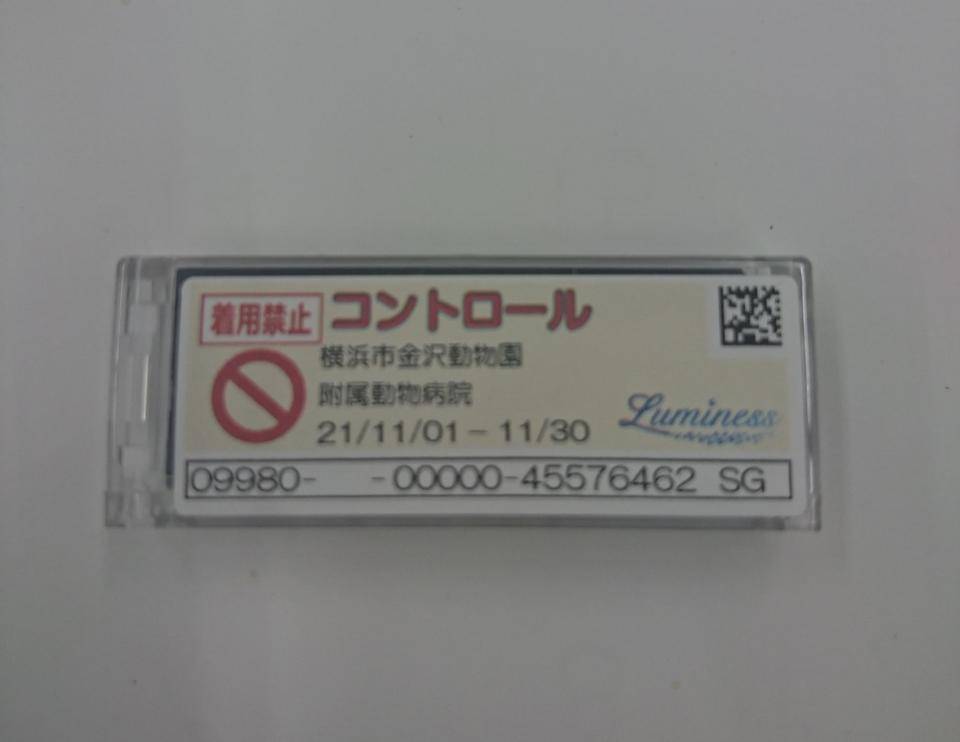

防護服から手などはみ出ている部分もありますし、我々は毎月、どれくらい放射線を浴びているかを測定するバッチを身に付けています。

(比較対照用のコントロールバッチ。身に着けているバッチにはそれぞれ個人の名前が入っています。)